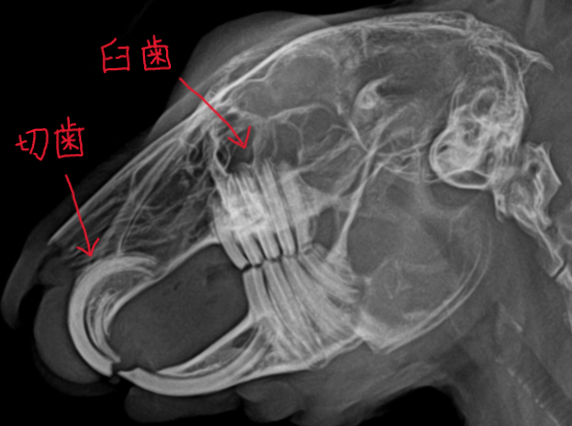

ウサギ・モルモット・デグー・チンチラなどの草食小動物にある、切歯(前歯)と臼歯(奥歯)は生涯伸び続けます。

当院では専用のダイヤモンドディスクを用いて切歯を削ります。

臼歯の処置は専用のドリルや臼歯用鋏を使って行います。